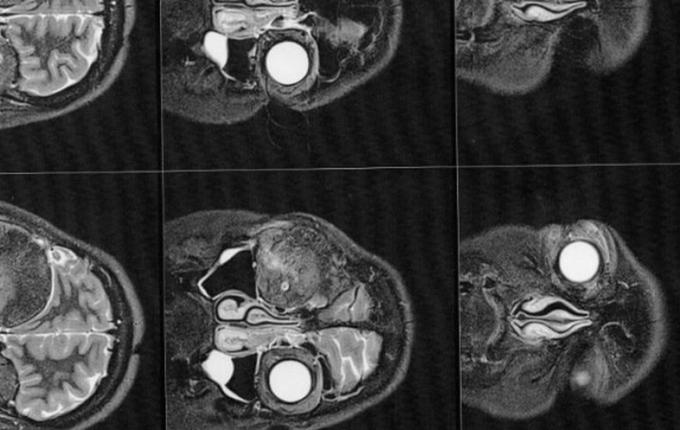

1 ano e 7 meses após o nascimento da Manuela (hoje com quase 4 anos), mais precisamente em dezembro de 2018, Gisele foi em busca de um neurocirurgião que estivesse apto a realizar a cirurgia. Optou-se por um médico da região, pela facilidade de locomoção. Por sua vez, por meio de exames de imagem, este médico a diagnosticou com um meningioma intraósseo (tumor cerebral benigno que se origina nas células das meninges).

Então este médico solicitou exames de imagem (ressonância magnética e tomografia) para avaliar a situação, os quais foi constatado que o meningioma ainda está ali, e que continua empurrando o olho e se expandindo para outras áreas. Trata-se de um meningioma gigante (medindo 6 x 6,6 x 6 cm), que está localizado na placa do assoalho da fossa média e anterior.

A cirurgia deverá ser feita de urgência, pois o meningioma continua se expandindo, e pode comprimir o olho esquerdo afetando a visão que lhe resta. Também pode comprimir outras partes do cérebro, ou pior ainda, causar a morte.